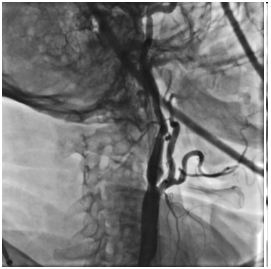

Выполнена аспирация 60 мл крови через систему церебральной протекции с получением атеросклеротического дебриса до получения «чистой» крови. Поочередно произведено снижение давления в дистальном и проксимальном баллонах системы, антеградный кровоток по правой ВСА восстановлен. Интракраниальные отделы хорошо кровоснабжаются из бассейна правой сонной артерии.

МРТ головного мозга в режиме DWI в 1-е сутки после операции: очагов повышенного МР-сигнала в веществе головного мозга не выявлено в режиме DWI b =1000.

В ближайшем и отдаленном послеоперационном периоде (3, 12 месяцев) –регресс неврологической симптоматики, данных за рецидив «преходящей слепоты» нет. По данным СКАД (на фоне прежней гипотензивной терапии среднее АД составляло 125/70мм.рт.ст. (145/80мм.рт.ст. до вмешательства).